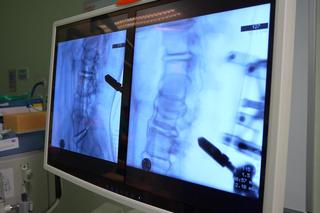

Nowoczesny system robotycznej nawigacji służy neurochirurgom ze Szpitala Wojewódzkiego w Szczecinie od lutego 2022 roku. W tamtym czasie placówka przy ul. Arkońskiej była trzecim szpitalem w Polsce, w którym pacjenci zyskali możliwość skorzystania z tak nowoczesnej technologii przy operacjach kręgosłupowych. Do dzisiaj robot wspomógł specjalistów w ponad 100 zabiegach. To prawdziwy rekord, gdyż żaden zespół w Polsce nie wykonał ich więcej.

Największą zaletą systemu jest jego precyzja. Robotyczne ramię sterowane przez lekarza, w parze ze szczegółowym mapowaniem organizmu pacjenta w technologii 3D, pozwala na precyzyjne umieszczenie implantu w wybranym miejscu.

– Osadzenie każdego jednego implantu w kręgosłupie wymaga od neurochirurga idealnej niemal precyzji. Jeśli któryś z tych implantów miałby znaleźć się w nieidealnej pozycji, to następstwa dla pacjenta bardzo często są opłakane – dodaje dr Sałapa. – Robotowi nie drżą ręce, więc ma nad lekarzem pewną przewagę. Potrzebne jest jednak doświadczenie, które nasz zespół nabywa od ponad 1,5 roku, by tym ramieniem odpowiednio operować.